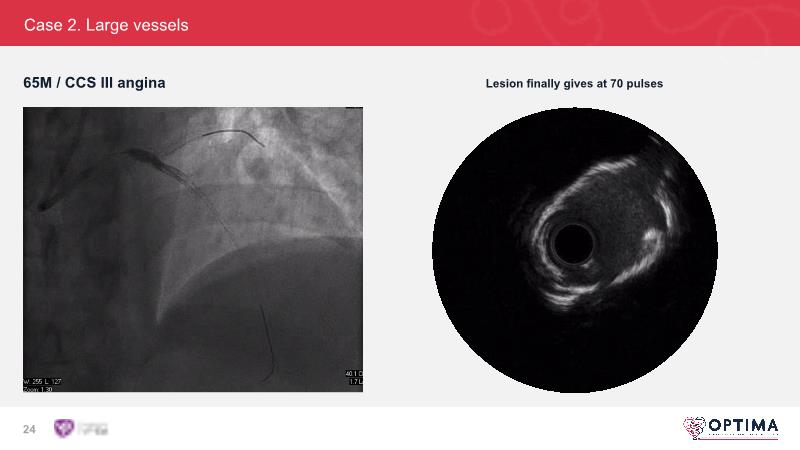

Cracking calcium: intravascular lithotripsy’s unique mode of action in treating calcified lesions – What's the evidence?

Watch this GulfPCR-GIM 2022 session to understand the unique mechanism of action of IVL, the use of intravascular imaging in calcium identification, the gender gap, disrupted CAD trials, and the evolution of treatment of calcified lesions together with the role of IVL.

- To be familiar with intravascular lithotripsy and its unique mechanism of action and the use of intravascular imaging in identifying calcium